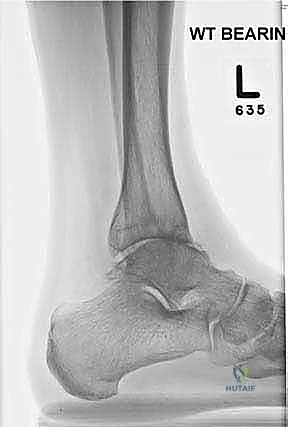

- الأشعة السينية الحاملة للوزن (Weight-Bearing X-rays): هي المعيار الذهبي المبدئي. تظهر تضيق المسافة المفصلية، تكون النتوءات العظمية (Osteophytes)، والتكيسات العظمية (Subchondral cysts).